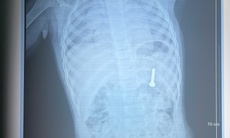

Kết quả thăm khám và điện cơ cho thấy, người bệnh bị tổn thương dây thần kinh mác sâu bên trái. Đây là nguyên nhân trực tiếp dẫn đến tình trạng trên. Bệnh nhân được chẩn đoán liệt dây thần kinh mác và nhập viện điều trị.

Bác sĩ châm cứu cho bệnh nhân.